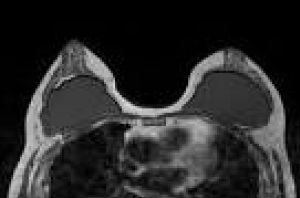

Магнитнорезонансно изследване на протезирани гърди

Естетичната и онкологична хирургия все по-често използва импланти за целите на аугментационна и онкологична мамопластика, което поставя остро въпроса за адекватна визуализация на протезата и подлежащата жлезна тъкан.

Целта на проекта е да се разработят и въведат в ежедневната практика секвенции, които да визуализират селективно силикона и да подтиснат сигнала от водата и меките тъкани.